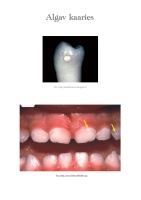

Lutipudelikaaries

Hambakaariesest, on ohustatud ka imikud ja väikelapsed, kellel võimaldatakse vanemate/hoidjate poolt kogu päeva jooksul imeda lutipudelist mahla, piima, vt. suhkruid sisaldavaid jooke ja keda pannakse magama magusa joogiga lutipudelis!

Lastel, kellel esineb hambakaariest varases eas on suurem risk hammaste lagunemisele ka hilisemas elus. Seetõttu on väga oluline vältida hammaste lagunemist hambasõbraliku toitumise, hea suuhügieeni ja fluoriidide kasutamise kaudu.

Nende laste ülemiste esihammaste asemel laiutavad suus inetud mustad tüükad, mis põhjustavad valu ja ebamugavustunnet. Hambaravis nimetatakse selliseid hambaid “lutipudeli kaarieseks”. Nende hammaste ravi on raskendatud nii laste vanuse kui ka piimahammaste anatoomiliste iseärasuste tõttu.